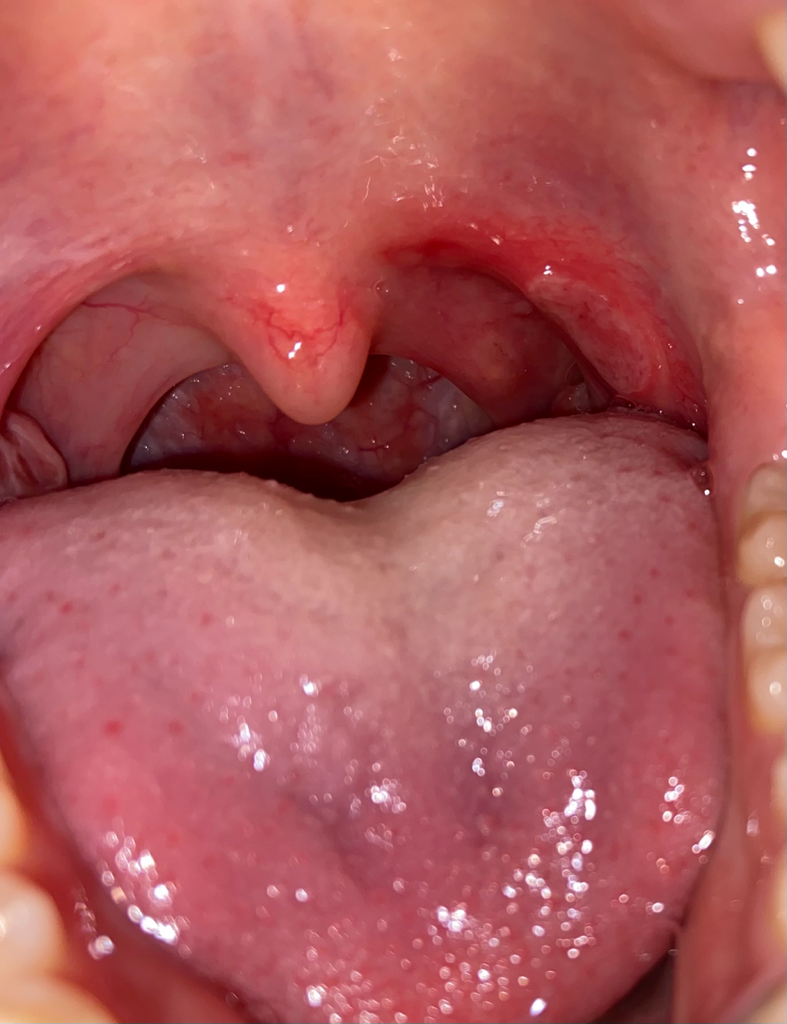

감기때문에 구내염인지 편도염인지 나서 미친고통때문에 약을 먹으려하는데요,

근데 첫번째 사진이 염증이 생긴지 하루 뒤고, 두번짜 사진이 그 다음날인 오늘인데 상처가 더 커졌습니다 ㅠㅠ

근데 구내염같기는 한데 제 감기약에는 관련된 약이 없는거죠? 구내염 약을 따로 사서 먹어야 할까요? 목이 가만히 있어도 타들어 가는 느낌이고 물먹을때나 밥먹을때는 진짜 고문 당하는 것 같아요 ..